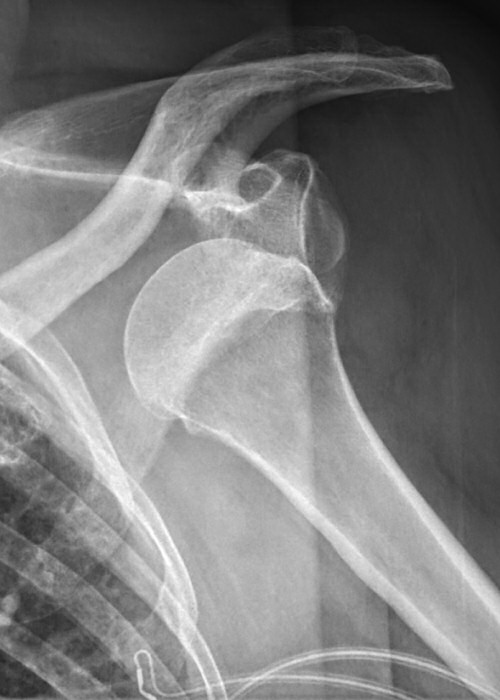

Bakre luxation, patienten hade mycket ont, kunde inte röra axeln alls. På frontalbilden ligger kaput roterat, på sidobild ligger kaput inte rätt i leden, på 3D-rekonstruktion syns felställningen tydligt (delar av nyckelben och akromion bortredigerade).